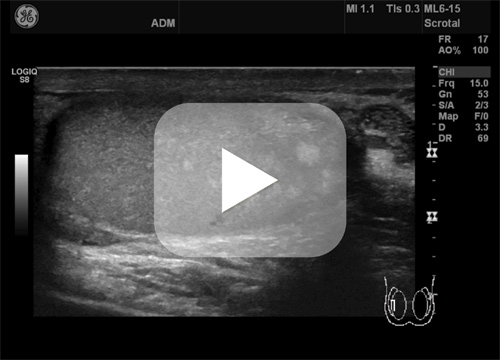

En frisk mann i 40-årene hadde spontane smerter i begge lyskeregioner og testikler og ble derfor henvist til ultralyd av fastlegen. Undersøkelsen viste tallrike, høyekkogene foci spredt i testiklene. Disse var diffust avgrenset, ikke skyggegivende og det ble ikke påvist dopplersignal. Lesjonene varierte i størrelse opptil ca. 5 mm. For øvrig var testiklene symmetriske og normalt store, hadde homogent ekko og sidelikt dopplersignal. Det var en 2 mm cyste i caput epididymis på venstre side, ellers ingenting å bemerke ved epididymis. Ingen tilleggsfunn. Bildet viser lesjoner med utseende som fettvev i testiklene, testikulær lipomatose. Dette må ikke forveksles med mikroforkalkninger som er vanligere og som regel ufarlig, men med en uavklart sammenheng med senere testikkelkreft (1).

Testikulær lipomatose er et patognomonisk funn som kan relateres til Cowdens syndrom, en sjelden, arvelig tilstand som er assosiert med økt risiko for utvikling av flere typer kreft (2, 3). På bakgrunn av dette funnet ble derfor pasienten henvist til utredning ved Seksjon for arvelig kreft, Oslo universitetssykehus. Andre differensialdiagnoser ved bilaterale, multifokale intratestikulære lesjoner er bl.a. germinalcelletumorer, leukemi, lymfom, metastaser, granulomatøs sykdom (sarkoidose, tuberkulose) og leydigcellehyperplasi (3).